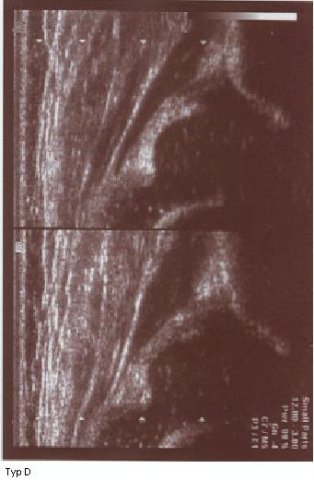

Typ D dach chrzęstny przesunięty

typ II/D powyżej żle oznaczony i wykreślony jak typ I ( kąt @ 62st kat B 55)trzeba uwazać ,podstawą oceny jest wygląd stawu podczas badania kąty tylko potwierdzaja rozpoznanie, w przypadku rozbieżności wygląd stawu decyduje wygląd nie wartość kątów

typ D poniżej

Typ D z wykreślonymi liniami

dach kostny bardzo niewystarczajacy;brzeg kostny spłaszczony

;dach chrzestny przesunięty dogłowowow ( szczyt głowy jest poniżej szczytu dachu chrzęśtnego)

dolne zdjęcia strzałki pokazują obrabek(czerwona):brzeg kostny (żółta);gałąż dolna(niebieska) ,

prawidłowy przebieg linii dachu kostnego(niebieska) stycznie do echa gałęzie dolnej i echa brzegu kostnego ;

linii dachu chrzęstnego (czerwona) stycznie do brzegu kostnego i przez środek geometryczny obrąbka i

linii podstawnej ( żółta)równolegle do sylwetki kości biodrowej po zewnetrznej stronie prze punkt gdzie ochrzęstne przechodzi w okostna i styka sie z echem kości